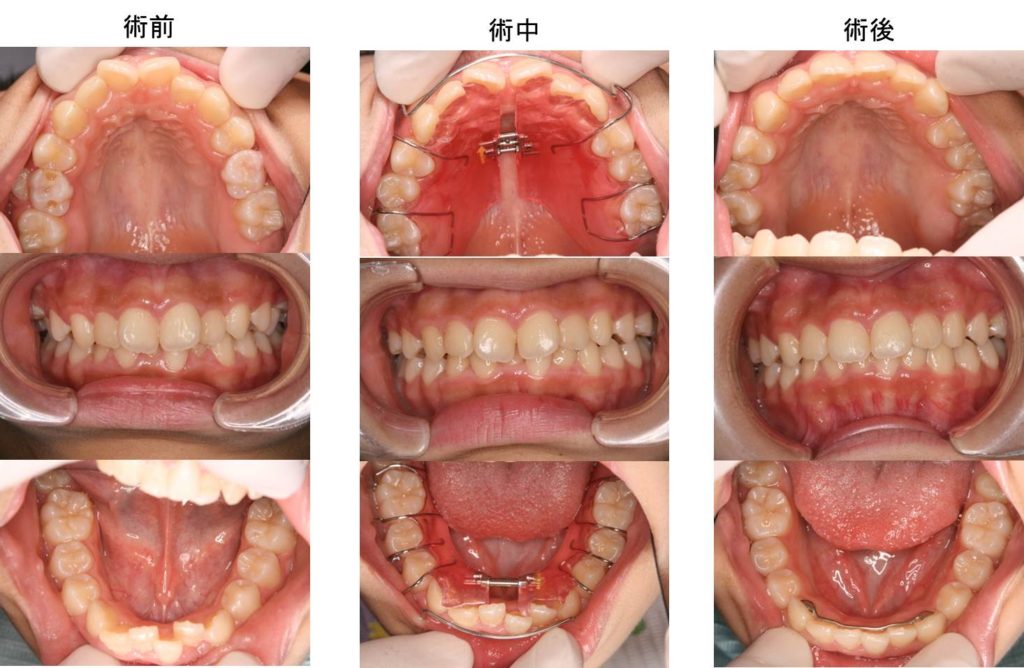

他院で矯正相談をしたところ、床矯正は無理で、乳歯が全部抜けてから本格矯正(ワイヤー&ブラケット矯正)になりますと治療方針の説明を受けたが、本人(中学1年生、女子)が取り外し式の床矯正を希望しているので何とかしてほしいとのことで来院されました。一番気になっている部分は、上の前歯が出っ歯に見える点で、次に気になるのは、下の前歯がガタガタであることでした。上下顎ともに歯の大きさに比べて顎が小さいので、床矯正装置で顎を広げていきました。上顎は床矯正装置のみで治療できましたが、下顎は、床矯正装置で顎を十分に拡大した後、下の前歯6本に4ヶ月間だけブラケットを装着し歯並びをきれいにしました。

治療費:¥400,000(税別) 治療期間:1年2ヶ月

副作用・リスク:リテーナーを正しく使わないと後戻りすることがある。